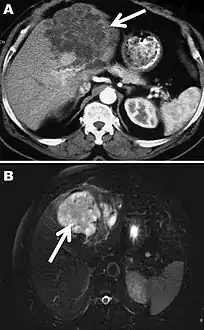

A formal diagnose of any type of echinococcosis requires a combination of tools that involve imaging techniques, histopathology, or nucleic acid detection and serology. For cystic echinococcosis diagnosis, imaging is the main method—while serology tests (such as indirect hemogglutination, ELISA (enzyme linked immunosorbent assay), immunoblots or latex agglutination) that use antigens specific for E. granulosus verify the imaging results. The imaging technique of choice for cystic echinococcosis is ultrasonography, since it is not only able to visualize the cysts in the body's organs,[20] but it is also inexpensive, non-invasive and gives instant results.[21] In addition to ultrasonography, both MRI and CT scans can and are often used although an MRI is often preferred to CT scans when diagnosing cystic echinococcosis since it gives better visualization of liquid areas within the tissue.[20]

As with cystic echinococcosis, ultrasonography is the imaging technique of choice for alveolar echinococcosis and is usually complemented by CT scans since CT scans are able to detect the largest number of lesions and calcifications that are characteristic of alveolar echinococcosis. MRIs are also used in combination with ultrasonography though CT scans are preferred. Like cystic echinococcosis, imaging is the major method used for the diagnosis of alveolar echinococcosis while the same types of serologic tests (except now specific for E. multilocularis antigens) are used to verify the imaging results. It is also important to note that serologic tests are more valuable for the diagnosis of alveolar echinococcosis than for cystic echinococcosis since they tend to be more reliable for alveolar echinococcosis since more antigens specific for E. multilocularis are available.[12] In addition to imaging and serology, identification of E. multilocularis infection via PCR or a histological examination of a tissue biopsy from the person is another way to diagnose alveolar echinococcosis.[20]